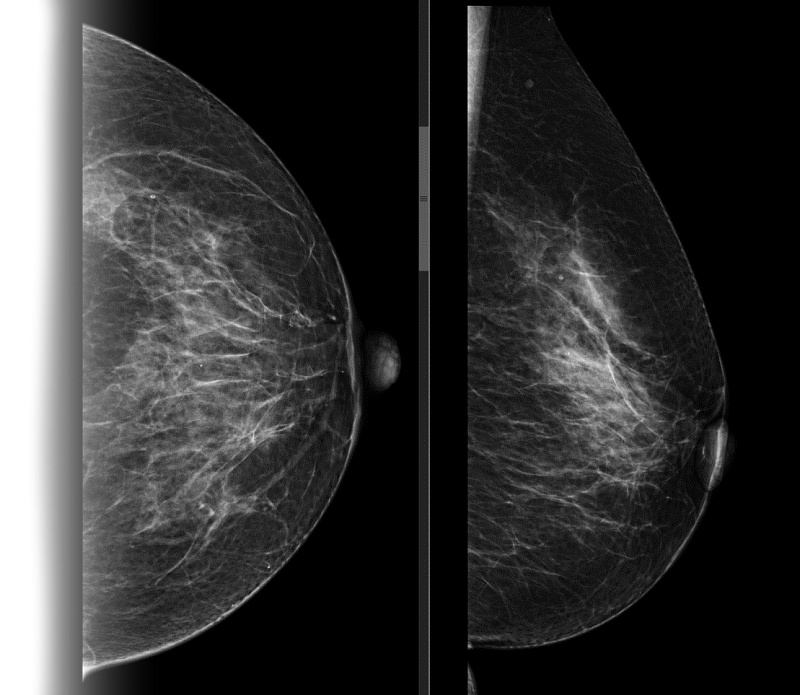

Маммография – это тип специального медицинского обследования, которое проводится с применением системы рентгена с малыми дозами облучения для исследования груди женщины (и мужчины - по показаниям).

Аппарат, на котором врач проводит данное исследование, называется — маммограф. Исследование на нем позволяет выявить болезни молочных желез на ранних стадиях, в том числе и такие опасные, как рак молочных желез.

Исследование проводится стоя, предварительно сняв верхнюю и нижнюю одежду области исследования, а также все украшения в области зоны интереса. Для получения четких и подробных снимков, молочную железу располагают между двух пластин маммографа, которые слегка сдавливая, фиксируют ее в неподвижном положении, добиваясь равномерного распределения тканей. Затем специалист делает снимок молочной железы в боковой и прямой проекции. Исследуются поочередно обе груди.